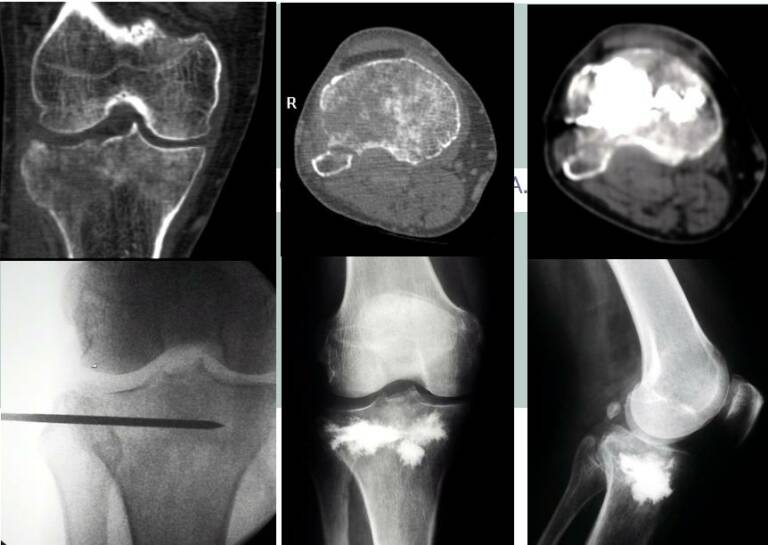

Cementoplasty is frequently combined with tumor ablation to:

Achieve local tumor destruction

Stabilize bone after ablation

- Reduce fracture risk

Image-guided percutaneous needle placement

Controlled cement injection within the lesion

- Real-time monitoring to ensure safe distribution